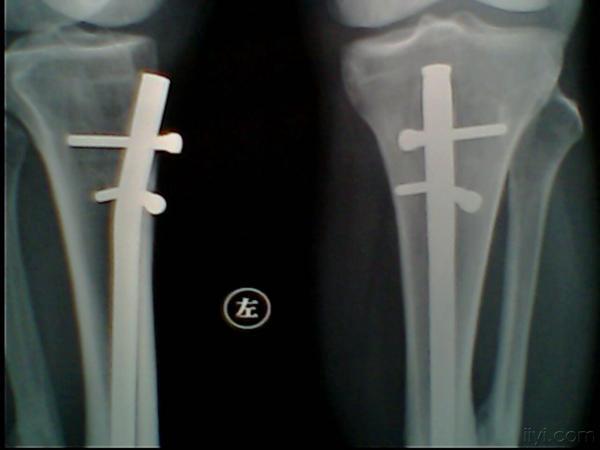

主 诉: 左胫骨骨折交锁髓内钉内固定手术后1年余

辅检:左胫骨骨折内固定术后

要求取出内固定物,如图

讨论:1、第二枚锁钉是弯了还是断了?

2、上下锁钉都没有问题,为什么中间的钉子有这样大的应力?